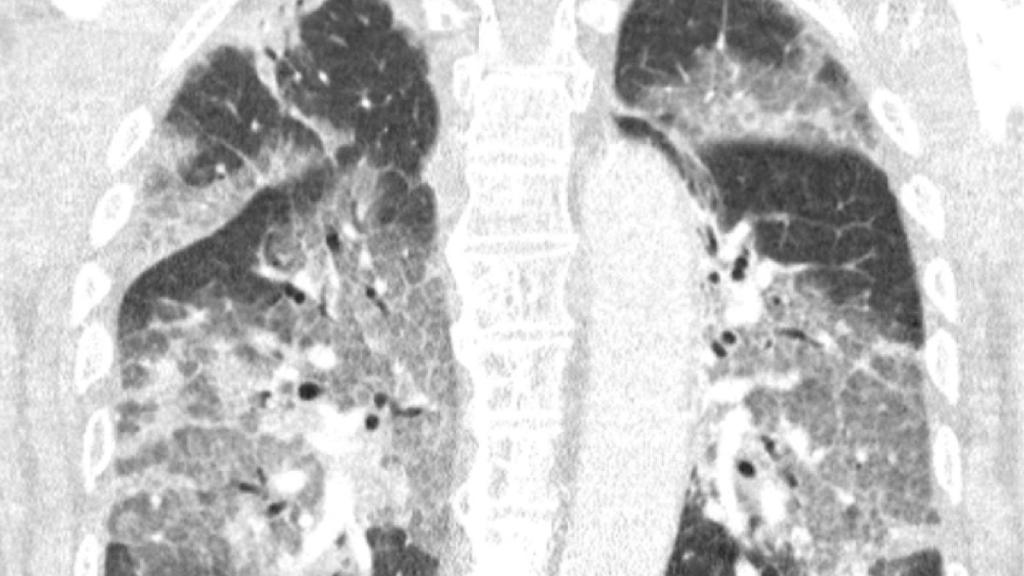

Escáner de los pulmones del paciente neerlandés al que se le había ofrecido una inyección de AstraZeneca.

Escáner de los pulmones del paciente neerlandés al que se le había ofrecido una inyección de AstraZeneca. Efe

La carta abierta de estos sanitarios neerlandeses, acompañada de una radiografía de los pulmones de su paciente que no deja indiferente, va dirigida al ministro de Sanidad en funciones, Hugo de Jonge, en una crítica a la paralización del uso de Janssen, filial de Johnson & Johnson, y de las limitaciones de edad impuestas al uso de AstraZeneca.

"Hoy ingresó en nuestro hospital el primer paciente que se había negado a recibir la vacuna de AstraZeneca tras toda la conmoción en la prensa. Oímos el tremendo pesar en su voz y la desesperación en sus ojos. El virus lo ha atacado y podría haberse evitado. Con su permiso, compartimos su escáner de pulmón. No es necesario ser un especialista en pulmones para reconocer la devastación, ni epidemiólogo para explicar los riesgos de no estar vacunado", alertaron.